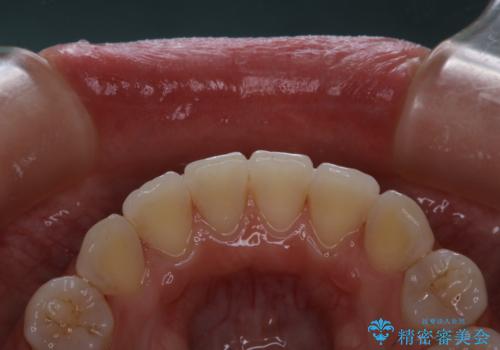

- 当院でのインビザライン矯正治療が終了し、メンテナンスにいらしている方です。PMTC30分コースを行いました。

矯正治療が終わり、せっかくきれいになった歯並びも、虫歯・歯周病などになってしまっては元も子もありません。

ご自身での歯ブラシ・セルフケアを行うと同時に、定期的なクリーニング(PMTC)を行うことで、いつまでも健康な歯を保つことができます。